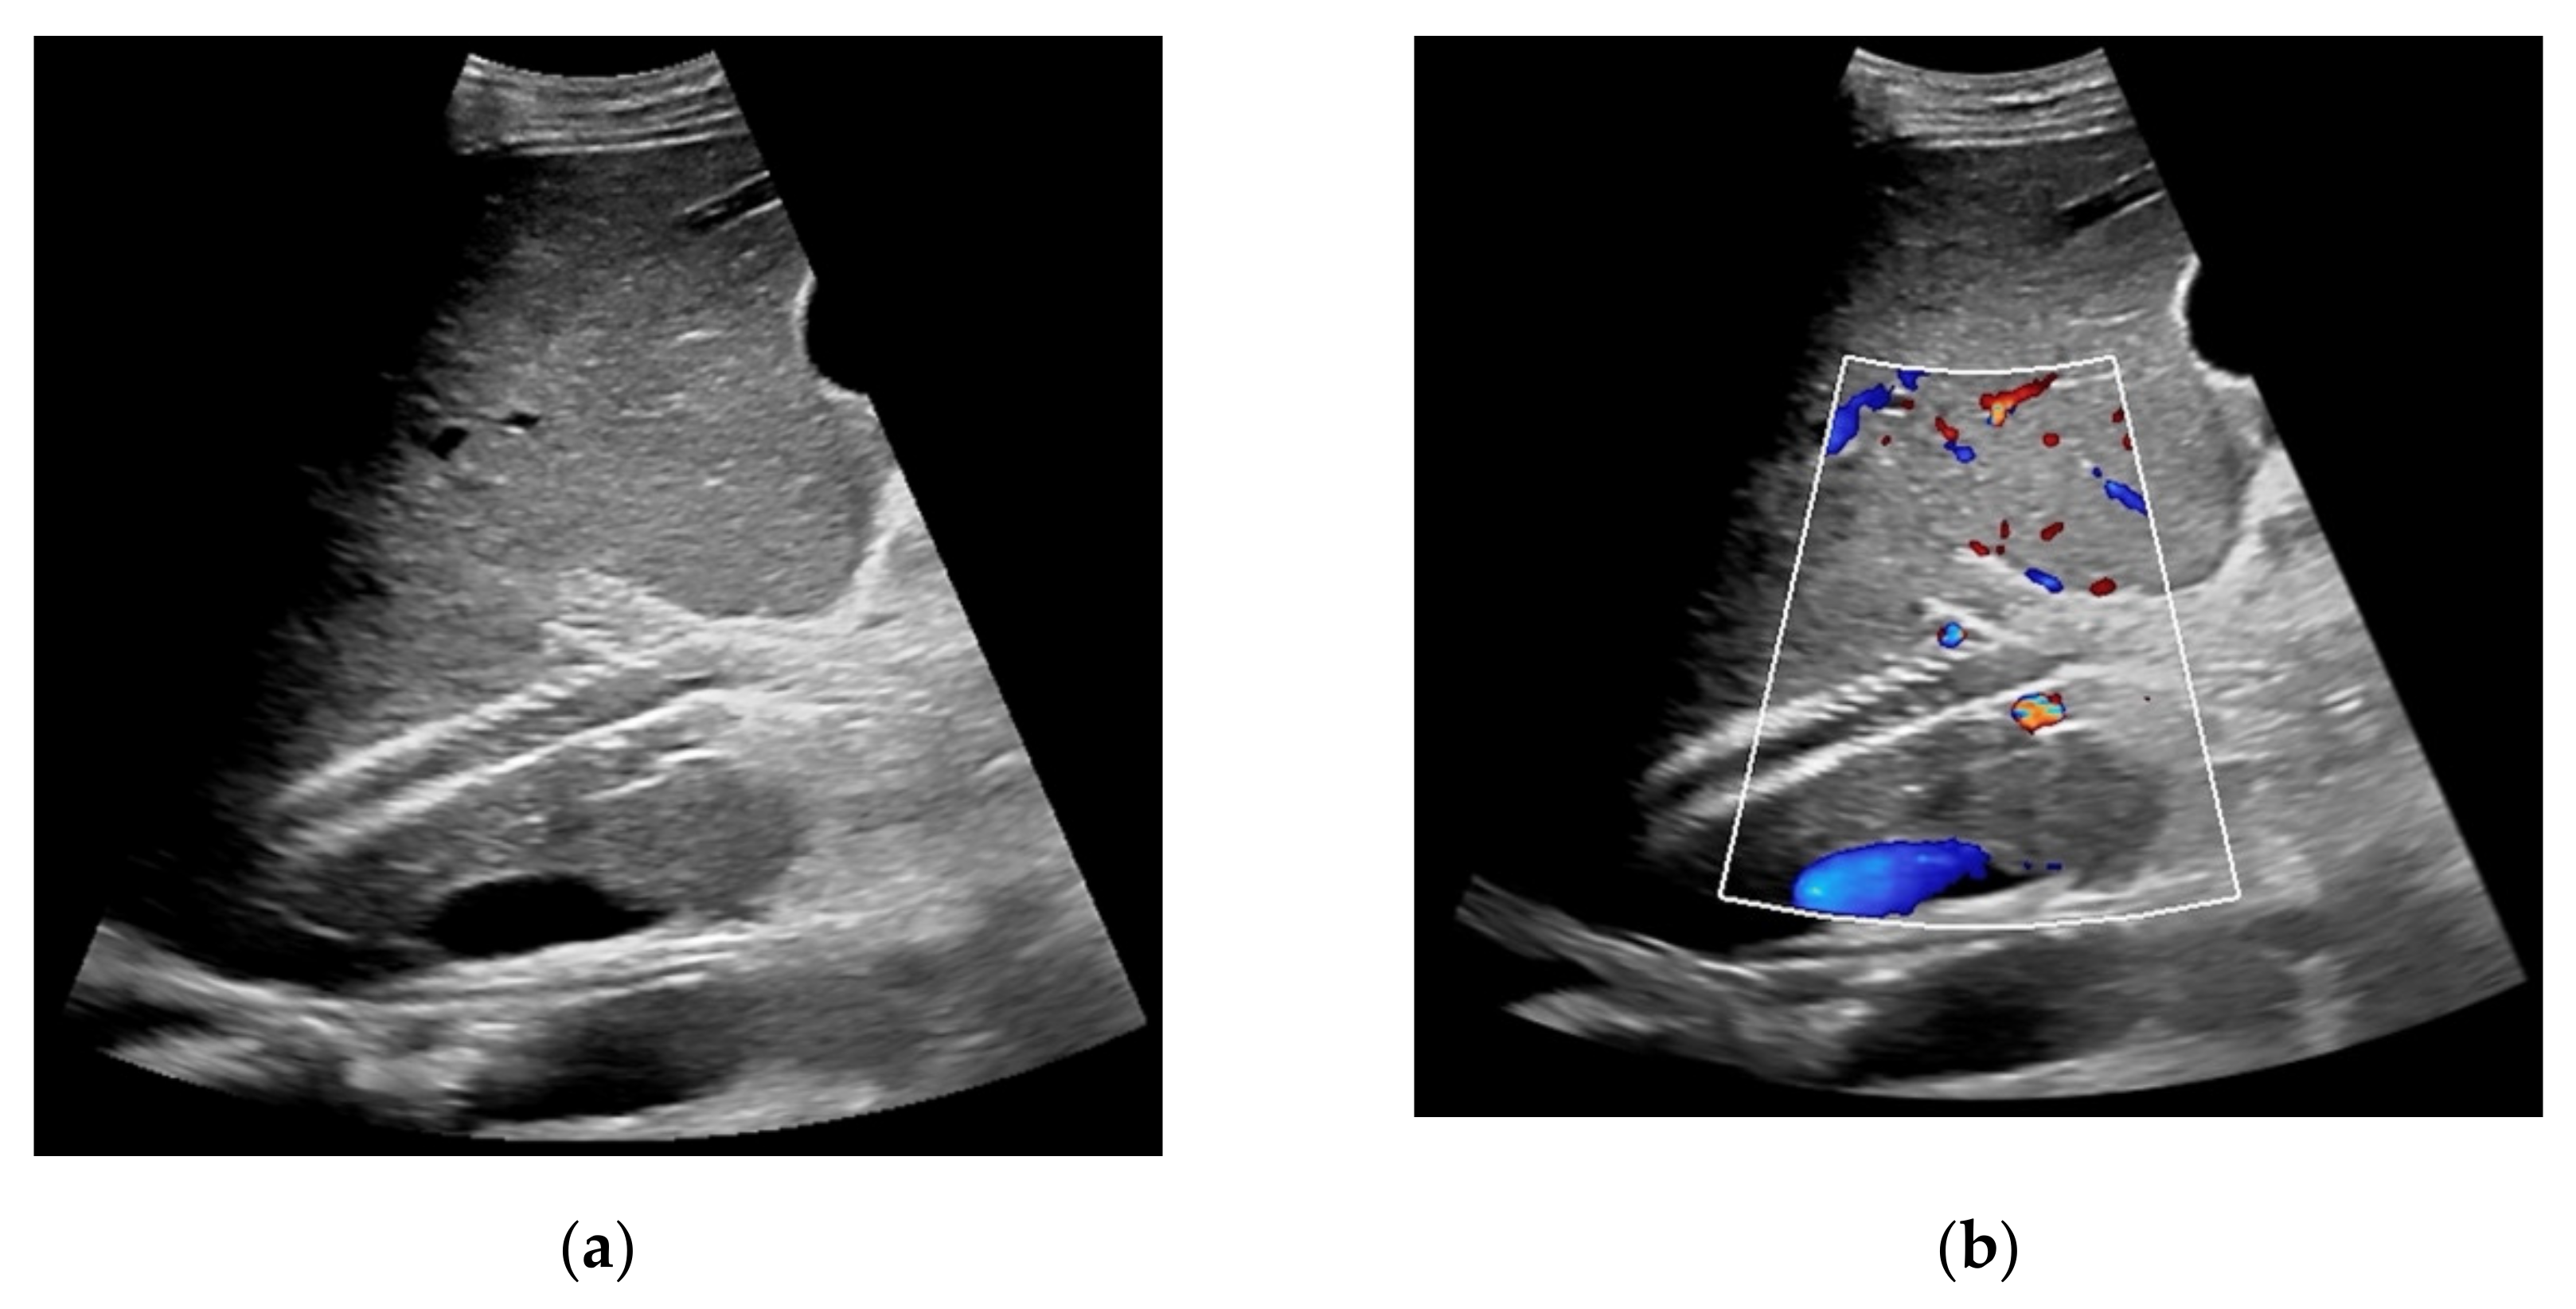

Figure 7. 52-year-old female patient with irregular presentation of the transjugular intrahepatic portosystemic shunt (TIPS) on B-mode ultrasound (a) and partial flow on Color Doppler ultrasound (CDUS) (b). After contrast administration, in contrast to CDUS, regular and continuous contrast of the TIPS is seen without evidence of thrombotic alterations or occlusion (c).